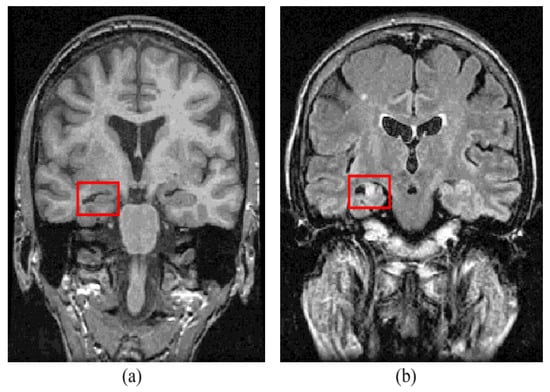

Figure 6 shows some regions of interest in the brain.

Figure 6.

Some of the ROI of the brain [60].